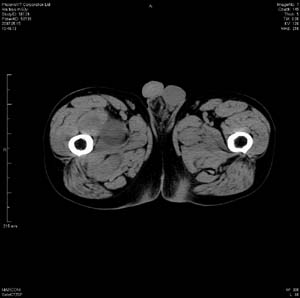

男 63岁 右大腿无痛性肿块11年,x片右大腿软组织肿块影,余无明显异常.ct值-13__239hu

右大腿股内侧股与收肌间隙间多发囊实性占位,界清.内示斑点状钙化.局部骨质无异常.肌肉推压移位表现.

考虑肌间隙病变.可有1,神经来源肿瘤.2,血管来源病变.3,淋巴来源肿瘤.4,脂肪来源肿瘤.5,滑膜来源肿瘤.结合病史只能考虑良性占位.建议增强或mri进一步分析.

同意,病史较长,病变周围分界清晰,考虑良性病变。病灶内有多发斑点状钙化,沿肌间隙生长,血管瘤或淋巴管瘤首先考虑。